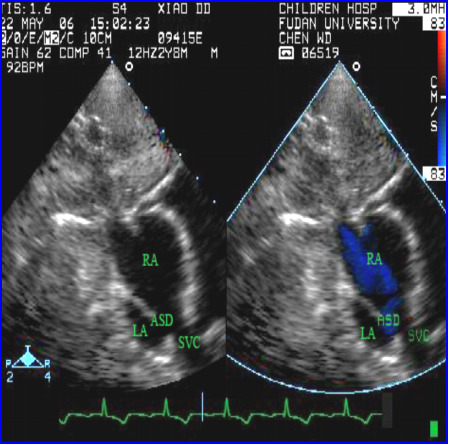

房间隔缺损(上腔型)合并右上肺静脉异位引流